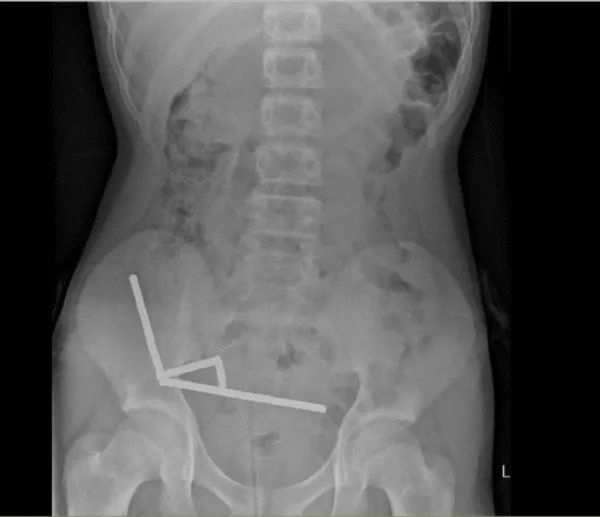

医生通过 X 光片观察到,男孩肠道的不同部位出现了四条线状的磁铁链。

腹部 X 光片显示了磁铁分布情况 来源:Lekamalage et al., NZMJ, 2025